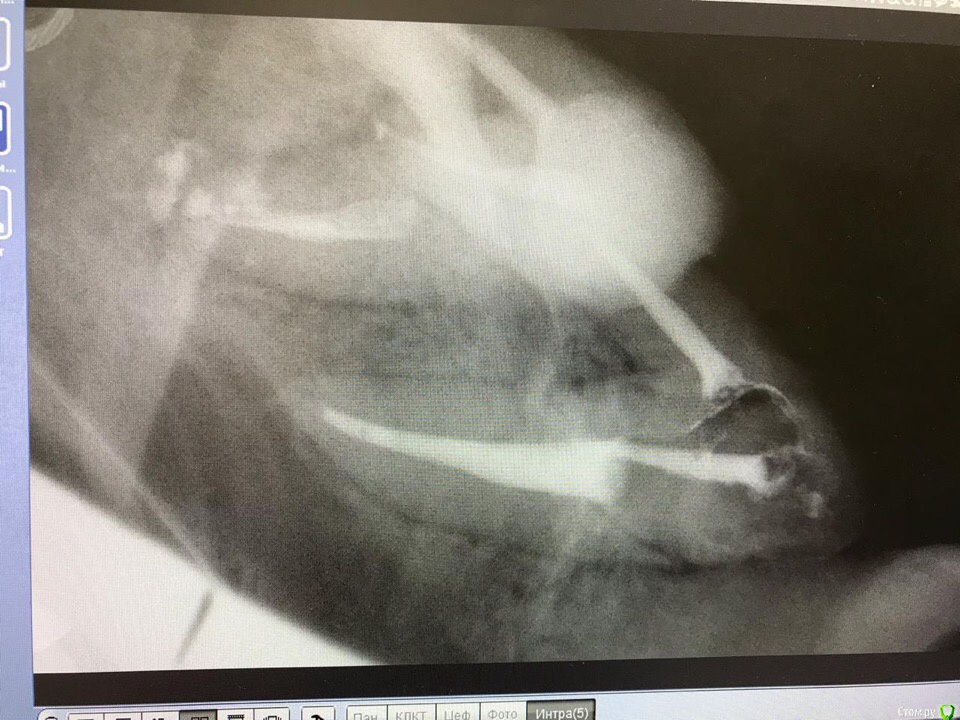

1586Doc Опубликовано 30 марта, 2019 Автор Поделиться Опубликовано 30 марта, 2019 (изменено) Еще немного работы45 зуб эндо и пломба и 46 зуб эндо и пломба на снимке справа Изменено 30 марта, 2019 пользователем 1586Doc Ссылка на комментарий